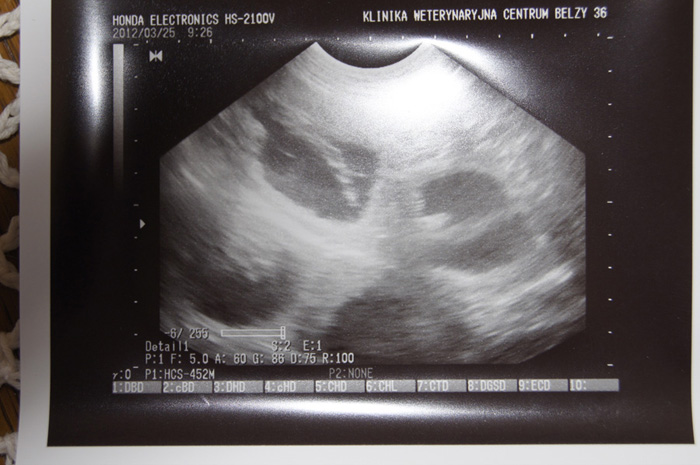

20-02-2012

Dziś został skonsumowany związek Sati z Fidelem, czekamy na efekty...